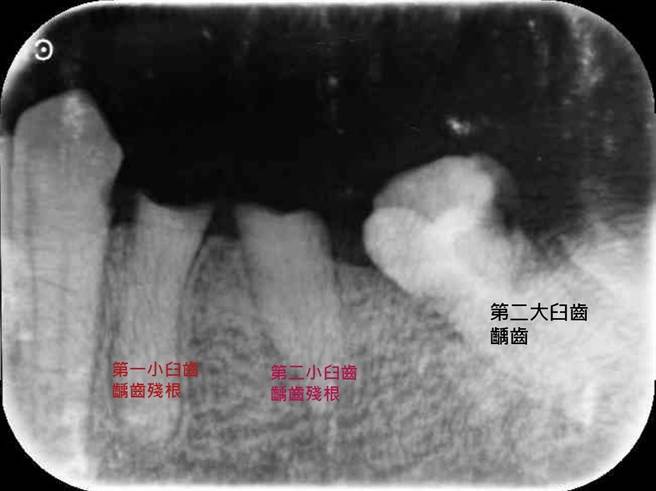

衛福部台中醫院牙科主任林佳詠表示,患者因超過兩年沒回診持續治療,這次到院時左臉已呈現嚴重腫痛,並出現呼吸急促的狀況,經確診為智齒齲齒殘根引發蜂窩性組織炎,台中醫院也啟動跨醫療科整合共治策略,聯合牙科、家醫科、精神科及麻醉科主治醫師共同制定治療方針,在進行全身麻醉的清創及多顆阻生齲齒殘根的拔除後,才終於穩定發炎疼痛情形,術後的住院照護也呈現良好的預後。

林佳詠指出,阻生埋伏智齒常因型態多樣變異,加上清潔照護不易,無法進行根管及牙周治療,一旦發生嚴重齲齒,極容易導致牙髓炎及牙周炎,更可能進一步惡化成蜂窩性組織炎,甚至是深頸部感染及路易氏咽頰炎,若沒有謹慎處理,就可能出現致命危險。